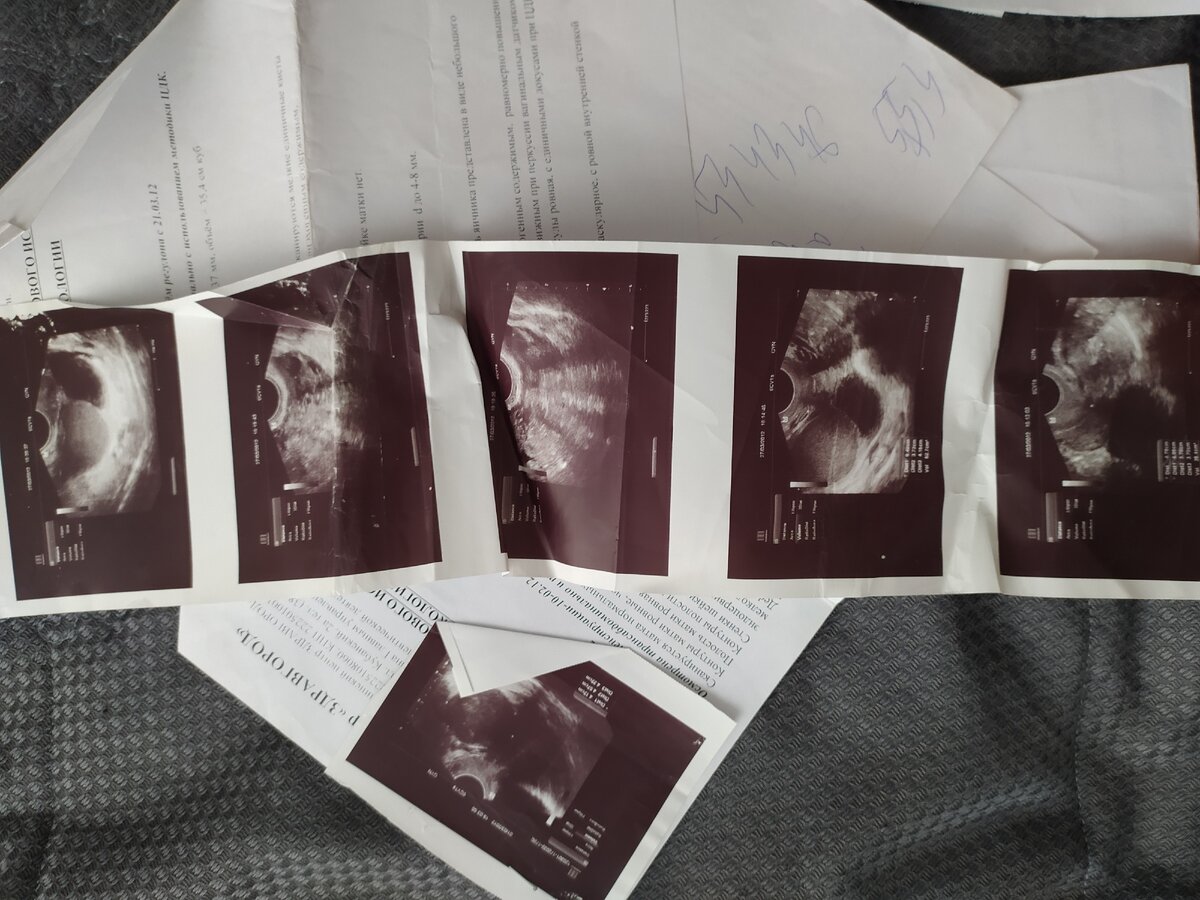

На следующий день, в 6 часов вечера я пошла на УЗИ. Это был верный шаг.

Как итог - в марте на УЗИ у меня опять находят кисту. Эндометриоидную (шоколадную) кисту.

В 2018 году у меня снова была операция. На этот раз -плановая. Убрали очаги эндометриоза из брюшины и проверили проходимость труб.

Трубы проходимы, но они извитые и деформированные. Матка есть, но в ней хроническое воспаление. Яичники есть, но они повреждены эндометриозом.